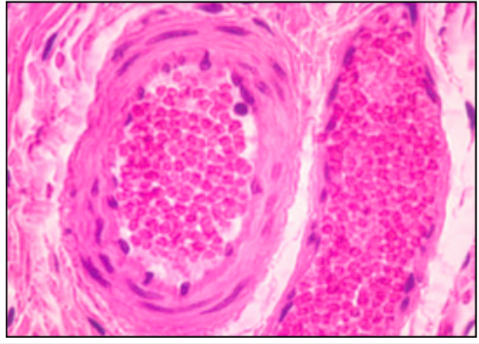

CAPILLARIES

- sometimes have contractile pericytes along bed

- continuous or fenestrated (gut, kidney glomerulus, endocrine glands)

- diameter is size of RBC

this slide - mature adipose